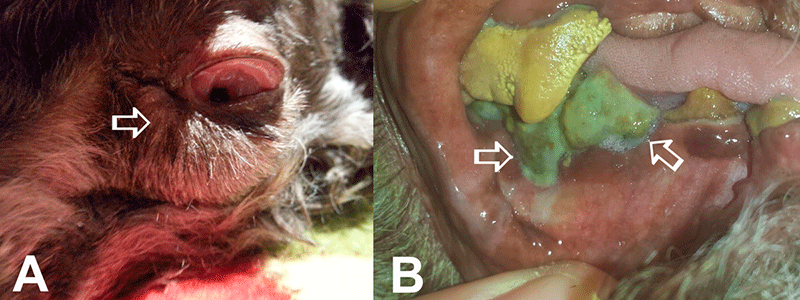

Postoperative complications after cataract surgery. A) Severe postoperative swelling of ocular and periocular structures (arrow) due to bad teeth was present in this patient, which developed one day after emergency lens removal surgery. B) Dental images from the same patient showed extensive dental tartar presence with inflammation and infection of gingiva (arrows). VISIT YOUR LOCAL VETERINARIAN AND DISCUSS DENTAL CLEANING PRIOR TO PURSUING CATARACT SURGERY!